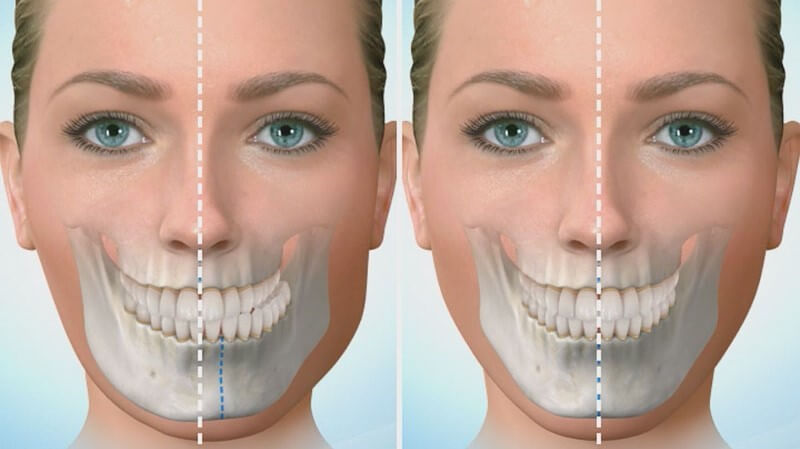

همراهان گرامی دکتر پیج، سلام. این بار در حوزه دندانپزشکی بر آن شدیم تا تنی چند از بهترین جراح فک و صورت در تهران را به شما معرفی کنیم. جراحی های این حوزه به سبب اصلاح بسیاری از ناهنجاریهای اسکلتی و دندانی جزئی و اساسی از جمله نامرتبی فک و دندانها انجام میشود. متخصص جراحی فک دهان صورت جراحی است که طیف وسیعی از بیماریها، صدمات و نقوص سر و صورت و فک و گردن و طاق جمجمه، بافت نرم و … را درمان می کند. خدماتی که جراح دهان و فک و صورت می تواند به شما ارائه بدهد شامل ایمپلنت (کاشت دندان)، جراحی های داخل دهانی، جراحی بینی، پلک و صورت، تصحیح خط خنده و جراحی دندان های نهفته و عقل می باشد.

اگر مشکلی در دندانها، فکها یا استخوانها و بافتهای صورت دارید که باعث ناراحتی شما میشود و شما را از انجام فعالیتهای عادی باز میدارد، ممکن است لازم باشد برای اصلاح ناهنجاری، تسکین درد، و بازگشت به زندگی عادی به یک متخصص جراحی دهان و فک و صورت مراجعه کنید.

جراح فک و صورت چه می کند؟

جراحان فک و صورت در درمان مشکلات و بیماری های مربوط به ناحیه سر و گردن تخصص دارند. بیماری هایی از جمله:

- فک نامرتب

- ناهنجاری نیش(دیسگناتیا)

·مشکلات اسکلتی

اکثر جراحان فک و صورت تا حدی می توانند به اصلاح مشکلات اسکلتی مانند نامرتب بودن فک ها کمک کنند. اگر درد مزمن مفصل گیجگاهی فکی که به عنوان TMJ شناخته می شود دارید، ممکن است دندانپزشک شما را به جراح فک و صورت ارجاع دهد.